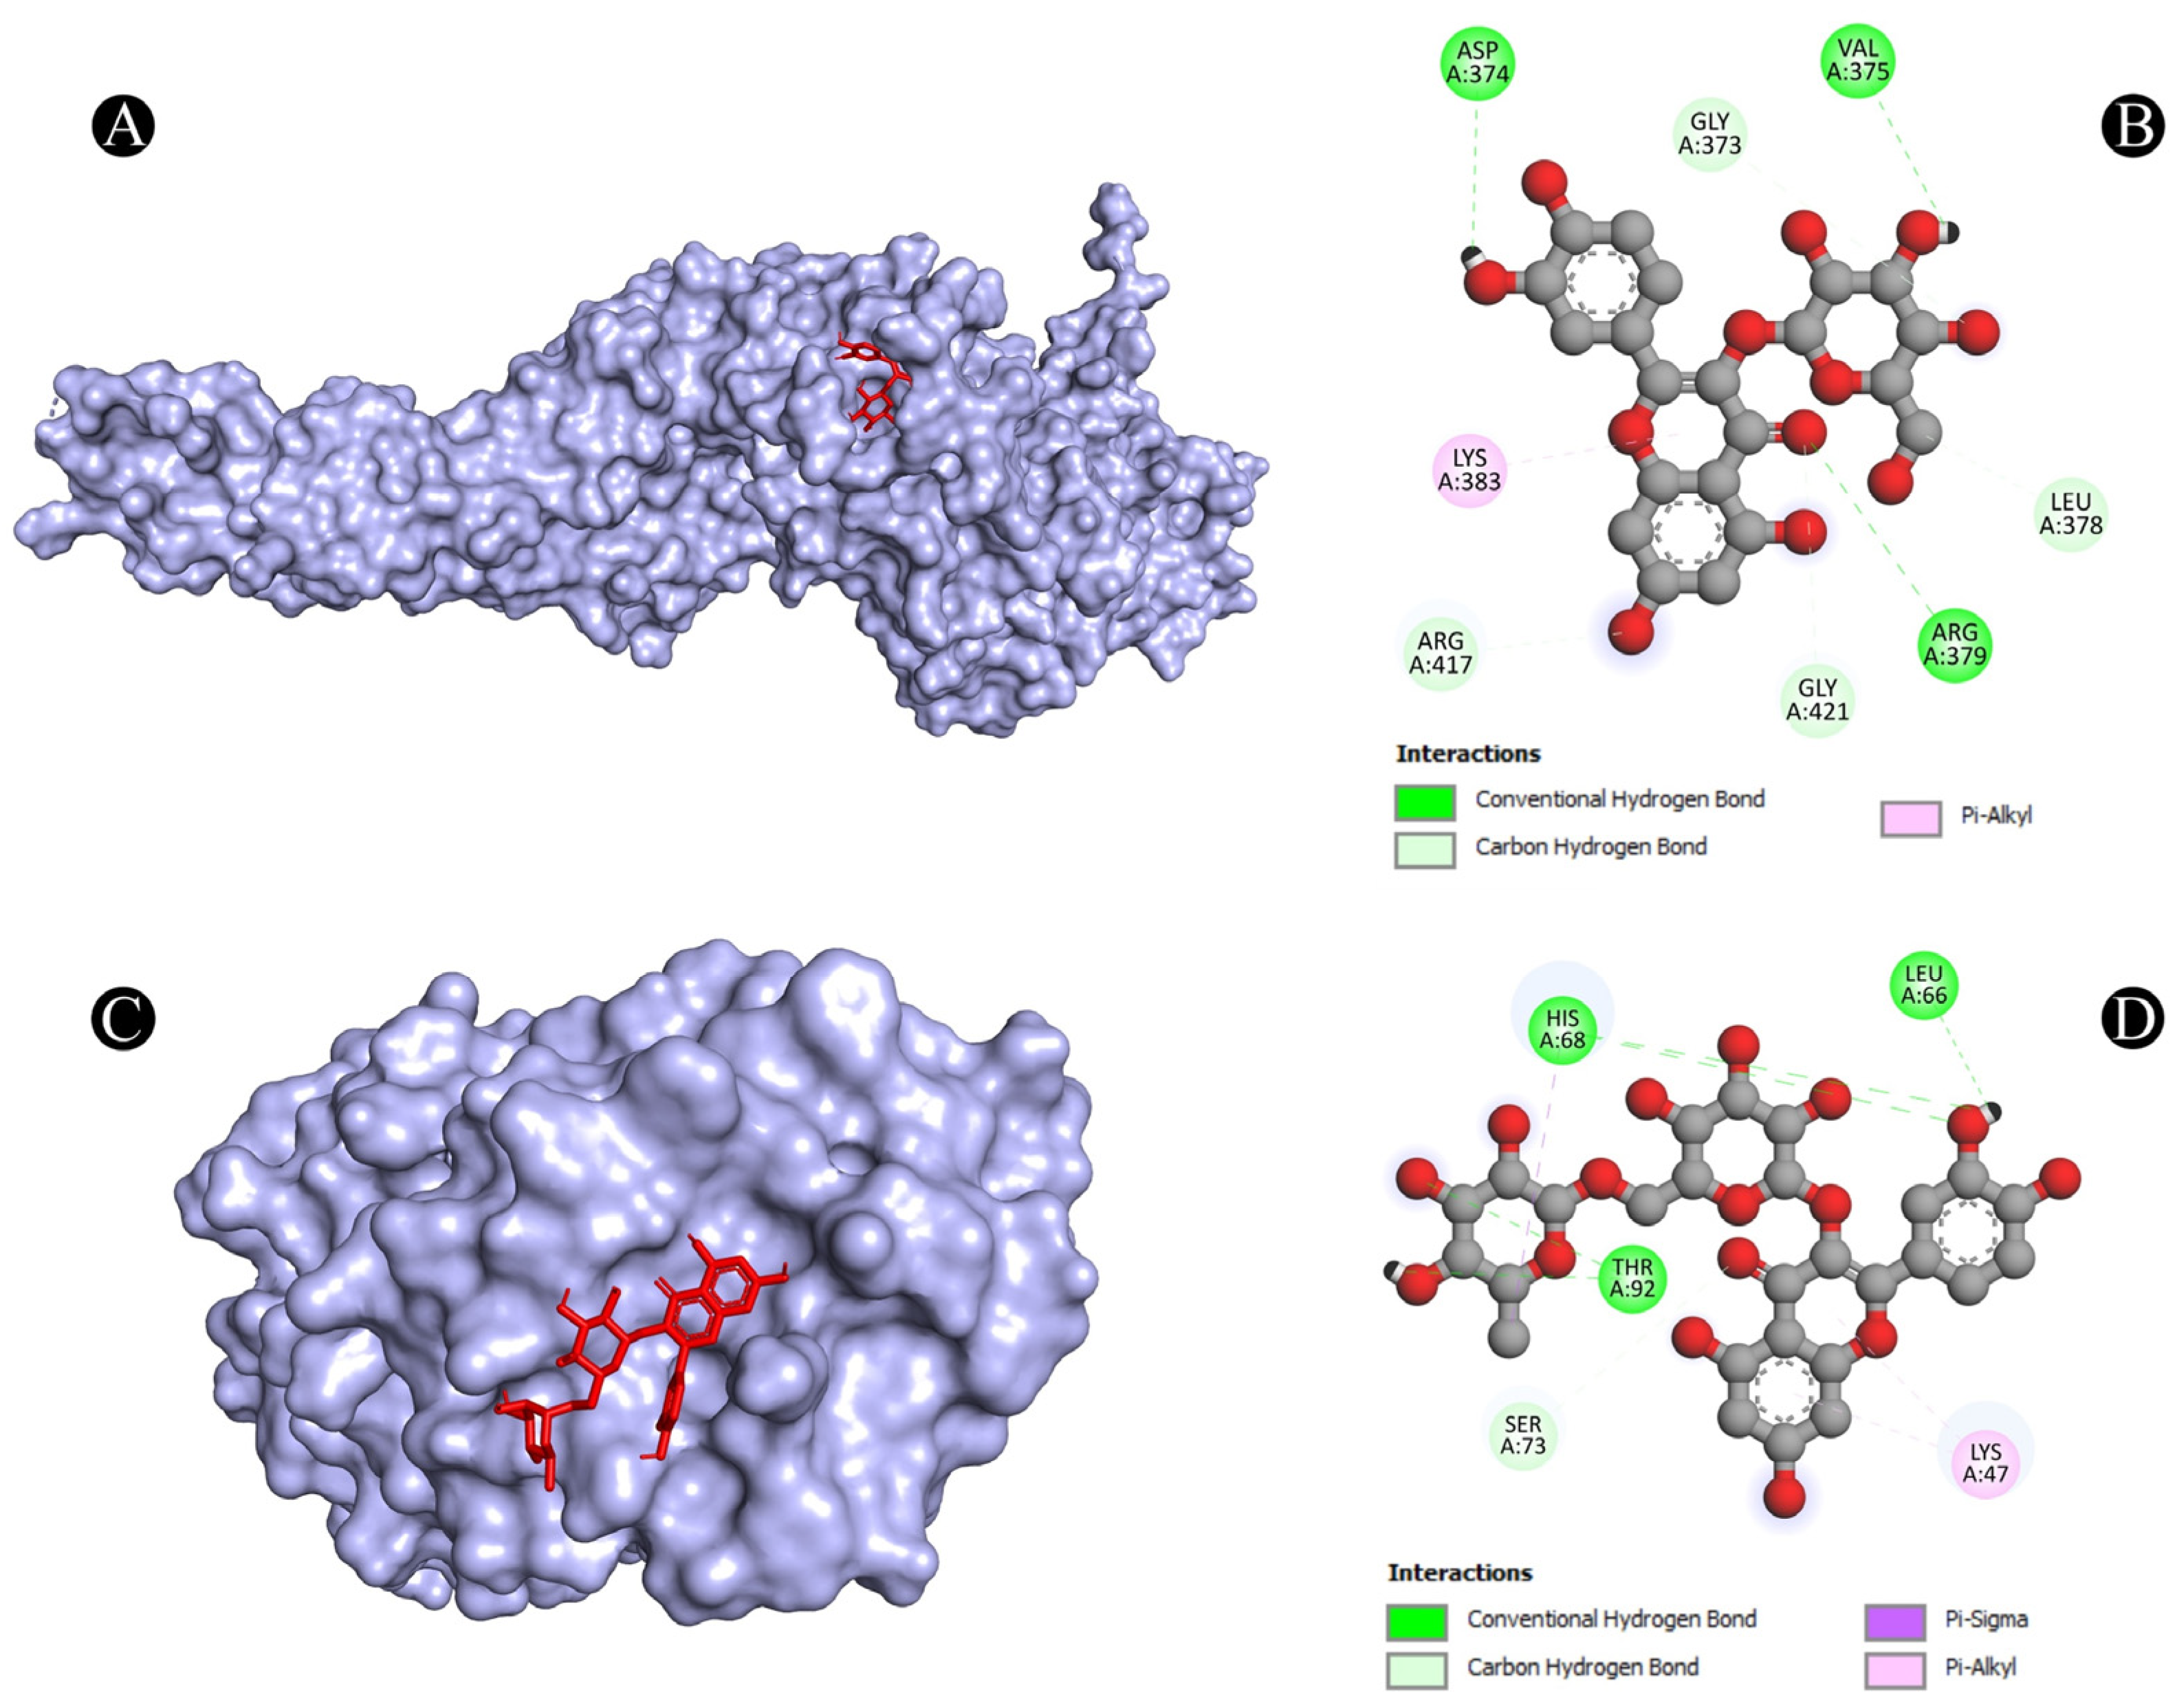

3.4. Molecular Docking Analysis

| 6 | STAT3 | A:ARG379:NH1-N:UNK1:O | Conventional Hydrogen Bond | 3.33961 |

| N:UNK1:H-A:VAL375:O | Conventional Hydrogen Bond | 2.64317 | ||

| N:UNK1:H-A:ASP374:OD1 | Conventional Hydrogen Bond | 2.35408 | ||

| A:GLY373:CA-N:UNK1:O | Carbon Hydrogen Bond | 3.45037 | ||

| A:ARG417:CA-N:UNK1:O | Carbon Hydrogen Bond | 3.42956 | ||

| A:GLY421:CA-N:UNK1:O | Carbon Hydrogen Bond | 3.39518 | ||

| N:UNK1:C-A:LEU378:O | Carbon Hydrogen Bond | 3.29566 | ||

| N:UNK1-A:LYS383 | Pi-Alkyl | 5.00243 | ||

| 7 | TLR4 | A:HIS68:ND1-N:UNK1:O | Conventional Hydrogen Bond | 3.03529 |

| A:SER73:CA-N:UNK1:O | Carbon Hydrogen Bond | 2.94848 | ||

| A:THR92:OG1-N:UNK1:O | Conventional Hydrogen Bond | 3.05155 | ||

| N:UNK1-A:LYS47 | Pi-Alkyl | 5.33037 | ||

| N:UNK1-A:LYS47 | Pi-Alkyl | 5.15142 | ||

| N:UNK1:C-A:HIS68 | Pi-Sigma | 3.88961 | ||

| N:UNK1:H-A:HIS68:O | Conventional Hydrogen Bond | 2.20639 | ||

| N:UNK1:H-A:LEU66:O | Conventional Hydrogen Bond | 2.34857 | ||

| N:UNK1:H-A:THR92:OG1 | Conventional Hydrogen Bond | 2.39563 | ||

| STAT3 (signal transducer and activator of transcription 3) | Suppresses inflammation and tissue damage caused by fungal infection | STAT3 is a transcription factor that can modulate the immune response and prevent excessive inflammation and tissue damage. STAT3 can also inhibit the growth and invasion of C. albicans by regulating the expression of anti-fungal genes and enhancing the phagocytosis of fungal cells. Ajwa date extract may stimulate the release of STAT3 and enhance its anti-fungal activity. | [90,91] |

| TLR4 (Toll-like receptor 4) | Recognizes fungal components and activates the inflammatory response against fungal infection | TLR4 is a protein that can recognize fungal components such as lipopolysaccharide and beta-glucan. TLR4 can activate the inflammatory response against fungal infection by inducing the expression of cytokines such as TNF-alpha, IL-1beta, IL-6, IL-12 and IL-23. Ajwa date extract may stimulate the release of TLR4 and increase its anti-fungal function. | [77] |